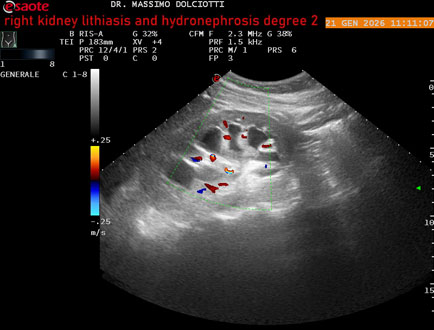

Data inserimento: 22/01/2026

Ecografia del: 21/01/2025

Strumento: Esaote MyLab Eight

Sonda: Convex Multifrequenza 1-8 MHz

Età Paziente: M 27 anni

Motivazione dell'esame: dolore al fianco destro da 3 mesi.

Commento all'esame: le immagini ed il video documentano il rene destro in sede, con ecostruttura disomogenea per evidenza, alla pelvi renale, di immagine iperecogena delle dimensioni di 16,2 mm, con cono d'ombra posteriore, da ricondurre a litiasi ed una formazione simile, di minore entità, al polo inferiore, delle dimensioni di 6,8 mm. Rene dx con diametro longitudinale di 122 mm (v.n. 90-120 mm) x 63 mm e parenchima renale dello spessore di 15 mm (v.n. > 13 mm). Rene dx con idronefrosi di 2° grado.

Conclusioni: litiasi e idronefrosi di 2° grado al rene destro (lithiasis and second-degree hydronephrosis of the right kidney).

In collaborazione: Dr.ssa Marica Manfredi - Ancona, Dr. Ilir Qose - Ancona

Presentazione: Dr. Massimo Dolciotti - Ancona

Elaborazione digitale: Andrea Dini - Ancona